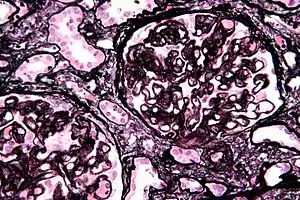

| Micrograph of membranous nephropathy showing prominent glomerular basement membrane spikes. Jones' stain. | |

- By light microscopy, the basement membrane is observed to be diffusely thickened. Using Jones' stain, the GBM appears to have a "spiked" or "holey" appearance.

- On electron microscopy, subepithelial deposits that nestle against the glomerular basement membrane seems to be the cause of the thickening. Also, the podocytes lose their foot processes. As the disease progresses, the deposits will eventually be cleared, leaving cavities in the basement membrane. These cavities will later be filled with basement membrane-like material, and if the disease continues even further, the glomeruli will become sclerosed and finally hyalinized.

- Immunofluorescence microscopy will reveal typical granular deposition of immunoglobulins and complement along the basement membrane.[18]